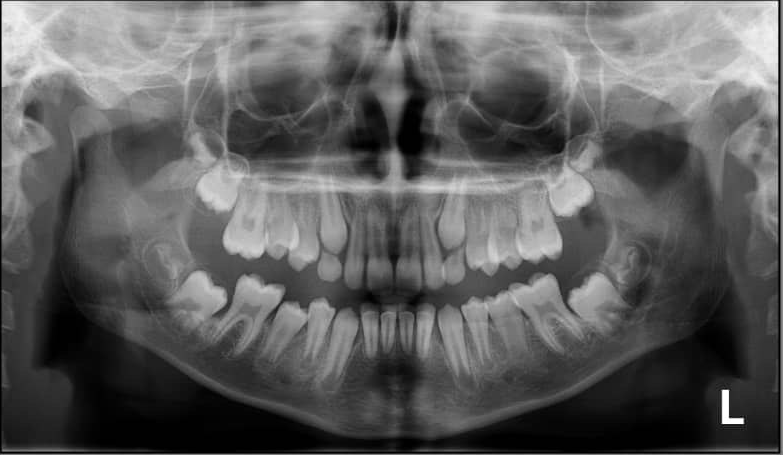

4. How old is the patient with the following X ray?